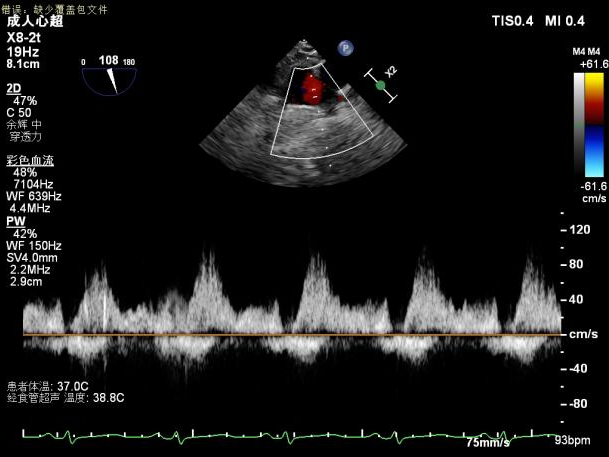

术后即刻超声提示二尖瓣反流下降至微量,二尖瓣平均跨瓣压2mmHg,多切面证实夹合组织充分,左上肺静脉多普勒波形由反向恢复正常。

2.X-plane切面调整瓣膜夹的位置:主要定位PISIA最明显的A2/P2区,分别二尖瓣交界联合切面和 LVOT切面调整夹子轴向,同时在3D切面上观察夹子方位和区域,瓣膜夹位置良好,轴向和方位均理想后,捕获A2/P2偏1区处的前后瓣叶,逐渐关闭瓣膜夹,TEE显示二尖瓣反流明显减轻至微量,3D视角显示组织桥连续完整,瓣叶抓捕稳定。彩色血流提示微量的瓣膜反流,测量平均跨瓣压差3mmHg,复查左上肺静脉血流频谱恢复正向,手术效果理想,逐步释放瓣膜夹系统撤出体外。